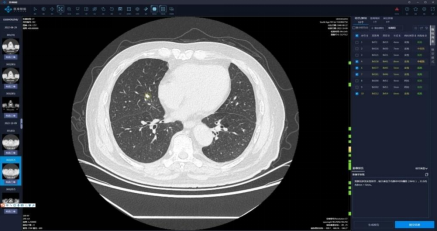

一、“胸部CT平扫+肺小结节AI辅助诊断”

上图是放射科开展的“胸部CT平扫+肺小结节AI辅助诊断”新业务,此业务启用人工智能肺小结节辅助诊断系统结合影像医师综合判断,为患者提供高效、准确的影像诊断服务。常规情况下,一个患者的肺部CT通常有几百张影像,医生凭借多年的阅片经验对其读片诊断需要10—20分钟,而使用"肺部AI智能分析系统"可大大缩减诊断时间,只需要几秒的就可进行初步诊断,而且"肺部AI智能分析系统"对1—3毫米的病灶还能做到瞬间定位,并会标示出病灶大小,位置,密度,初步分辩良恶性,自动生成结构影像报告供医生审查诊断。对于患者今后的随访复查也能提供精确对照。总体上,可大大提高了工作效率和准确率,同时减少患者的等待时间。此外,肺小结节辅助诊断系统可以自动匹配不同时间的同一病灶,并直观展示结节变化情况及趋势,为病灶定性及下一步诊疗提供影像依据。

适应症:任何有胸部体检需求的人群,尤其是肺内结节的筛查、定期复查、风险度的判定。

意义:基于AI的大数据支持,高效准确的提高肺内结节的检出及分析,无额外收费。